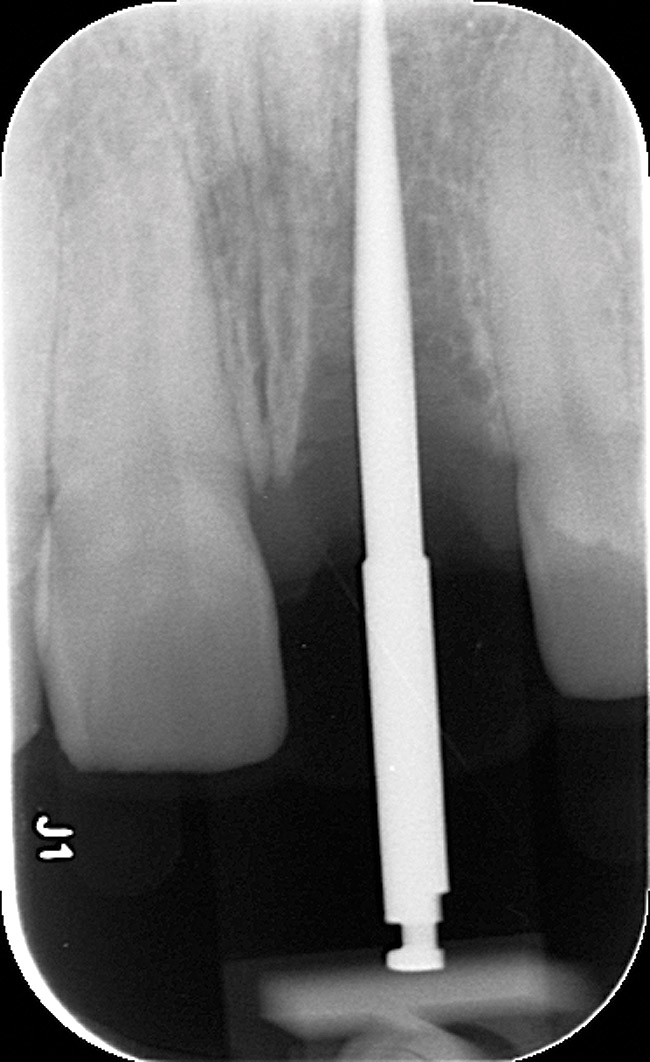

Radiographic evidence of external root resorption on tooth No. 26 and periapical radiolucencies with a history of prior endodontic treatment, including apicoectomies, were present on the mandibular central incisors (Figure 2).

Emergency endodontic treatment had been completed to manage the traumatically exposed root canal; Figure 10 shows the pre-treatment (Ellis Class III crown fracture) and post–endodontic-treatment periapical views of tooth No. 9. The restorative dentist temporarily cemented a glass-reinforced fiber post and used a fiber-reinforced composite core buildup material as an immediate provisional. Several weeks later, a provisional bis-acryl temporary crown on No. 9 was cemented on a larger-diameter glass-reinforced fiber post retaining a new fiber-reinforced composite core. Figure 11 shows the final feldspathic porcelain crown placed by the restorative dentist. During the fabrication and cementation of this crown, the remaining root appeared intact and the tooth was asymptomatic.

Figure 2  Initial periapical radiographs showing failed endodontic treatment of Nos. 24 and 25, and root resorption, No. 26.

Figure 2

Figure 10  Tooth No. 9, pretreatment, showing Ellis Class III crown fracture; completed endodontic treatment, provisional post and core—periapical views.

Figure 10